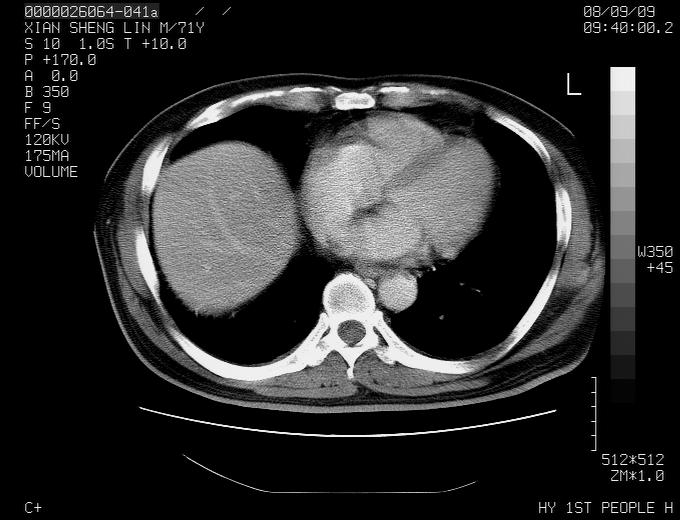

标题: CT15869:男性,71岁,因咳嗽而就诊,请讨论右上肺病变性质 [打印本页]

标题: CT15869:男性,71岁,因咳嗽而就诊,请讨论右上肺病变性质

患者,男性,71岁,因咳嗽而就诊,

典型的右肺中心性肺癌并纵隔淋巴结转移

考虑右肺中心性肺癌并右肺门及纵隔淋巴结转移。

1,右肺中心型ca,气管隆突旁淋巴结转移。

2,右膈明显抬高,建议肝脏扫描排除转移或原发灶。